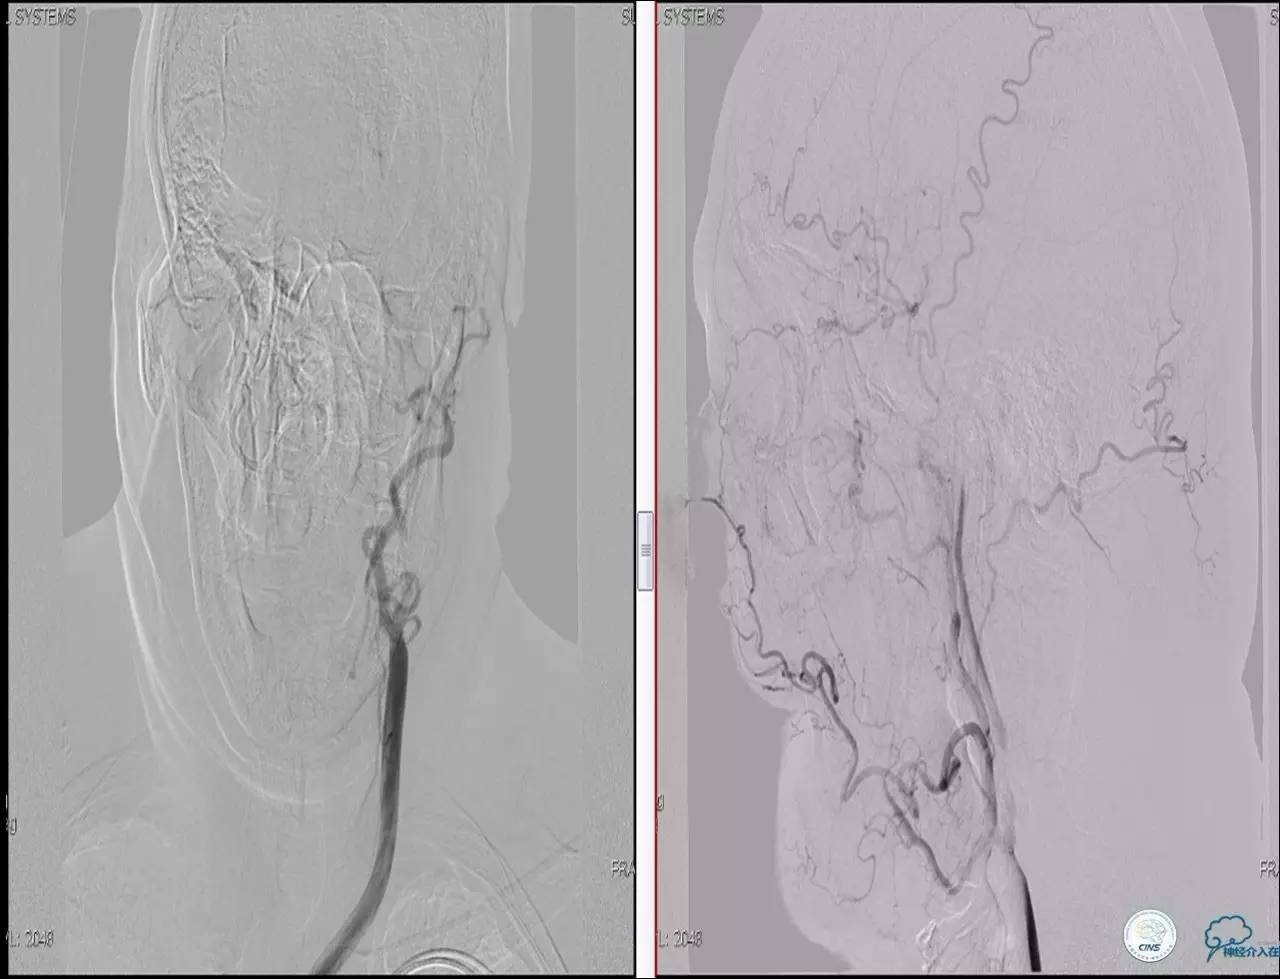

Case 3

》男,79岁。

》主诉:阵发性头晕伴双下肢无力一年余。

》查体:左侧上肢肌力Ⅱ级, 双侧下肢肌力Ⅲ级。

》既往史:高血压、糖尿病史。

》术后严密控制血压,未出现明显血压波动。

》术后三小时,患者出现恶心呕吐,伴有意识丧失。

》出血原因?侧支代偿不佳!